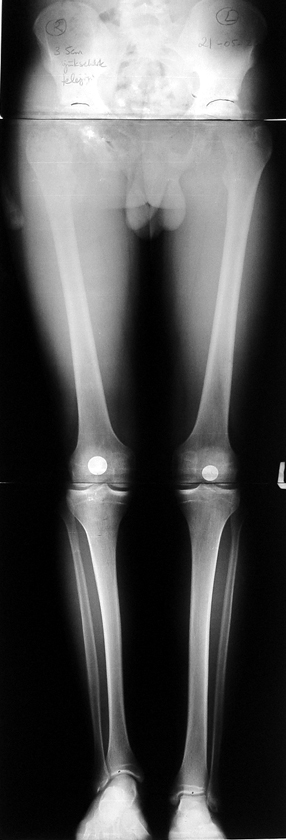

Bu Bacak Kısalık tipi bir kırığın kısalmış pozisyonda kaynaması ile oluşur. Bir çok vaka yetişkinlerde görülür ve sadece bir uzatma ile tedavi edilebilir. Ek deformiteler de aynı anda düzeltilebilir. Bu hastaların çoğu çivi üzerinden uzatma veya tam implante edilen çivi ile tedavi edilebilirler.